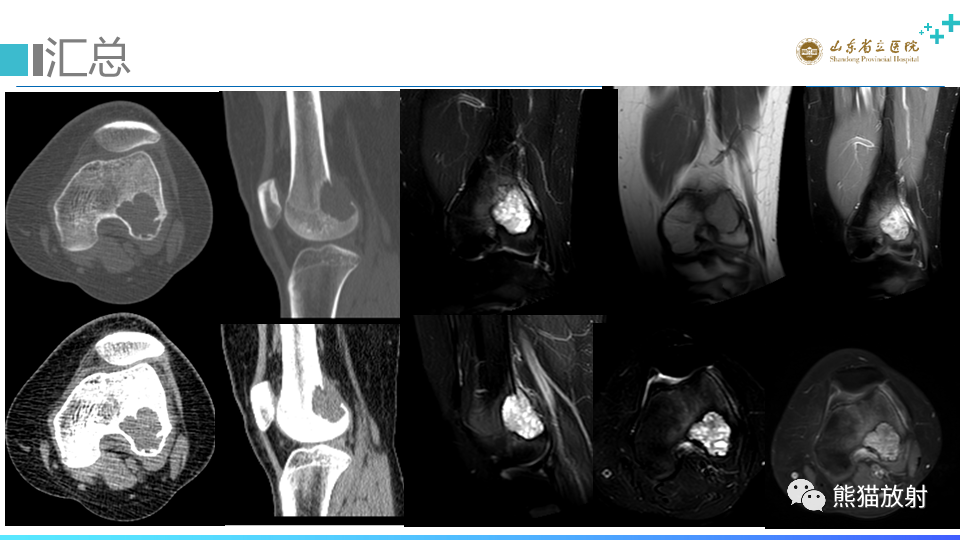

【病例】股骨远端动脉瘤样骨囊肿ABC VS 软骨母细胞瘤-1

【病例】股骨远端动脉瘤样骨囊肿ABC VS 软骨母细胞瘤-2